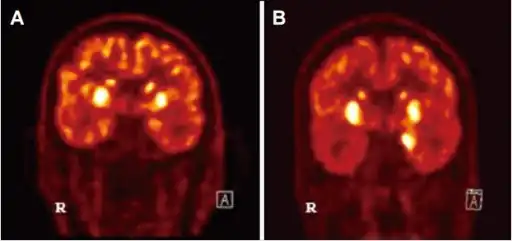

| Diagnosis of Autoimmune Encephalitis- a) basal ganglia hypermetabolism b) medial temporal hypermetabolsim | |